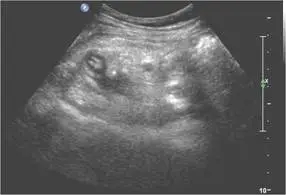

46歲女性病人主訴於月經過後下腹部疼痛,尤其右下腹部疼痛約3天,身體診察右下腹部有壓痛現象,右下腹部超音波檢查如圖,最可能的診斷為何?

- 第二張為同一構造的短軸切面,再次確認管腔置換、無蠕動,周邊偶可見少量游離液暗示局部炎性滲出。

以上影像符合急性闌尾炎的主要超音波徵象:盲端非蠕動管狀結構、外徑≥7 mm、壁層厚化及周圍炎性回聲增高,並有彩色多普勒顯示之局部高血流。